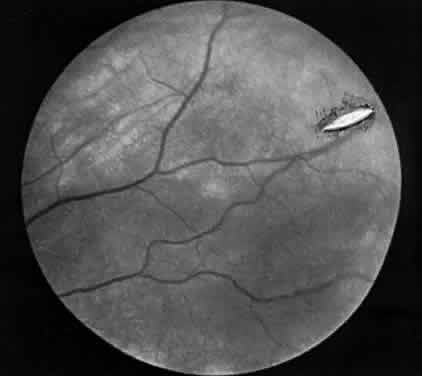

| Chorioretinitis sclopedaria refers to direct choroidal and retinal trauma

from a bullet wound in the orbital area. The bullet does not penetrate

the globe or the orbital wall; it lodges adjacent to the globe. Two

areas of the eye usually are injured by concussion: (1) the area adjacent

to the path of the bullet and (2) the macular area indirectly.17 One patient, observed during World War II, had a moderately large area

of chorioretinitis in the temporal equator from a bullet that had passed

between the sclera and the lateral orbital wall. Less often, an area

directly opposite the concussion site also can exhibit evidence of

chorioretinitis as a result of the contre-coup phenomenon. A peculiar syndrome secondary to trauma, usually of the perforating type that involves the lens, is pseudoretinitis pigmentosa. There is a selective loss of the photoreceptor layer,18 extinguished electroretinogram, and migration of pigment into the retina. These features may develop within a few days after the injury. FOREIGN BODIES Rarely, localized choroiditis is associated with penetrating intraocular foreign bodies as an isolated feature. The condition of the host, the manner of penetration, and the character of the foreign body must have been so correlated as to avoid the more devastating endophthalmitis. Relatively inert foreign material (e.g., glass, stone, quartz) may lodge in the retina and choroid and cause a low-grade inflammatory response that walls off the foreign substance. Such an inflammation may simulate other types of uveitis such as pars planitis and a Toxocara granuloma. A long quiescent period or intermittent recurrences of inflammatory signs may ensue. When a foreign body is nonmagnetic, systemic and periocular administration of steroids should be initiated and used in the follow-up treatment. Removal of a magnetic foreign body may be well tolerated in the choroid; its path through the eye often provokes vitreous damage and secondary retinal complications. RETINAL PERFORATION DURING SURGICAL MANAGEMENT OF STRABISMUS Hemorrhage initially covers the perforation site. Some of this hemorrhage may break through into the vitreous cavity but usually remains confined to the choroid and retina. In a day or two, bare sclera becomes visible, usually surrounded by residual hemorrhage and a rim of light pigmentation.19 It appears as if the choroid and the retina were scooped out, leaving bare sclera behind (Fig. 1). Inverted cutting needles seem responsible since this is a complication almost unheard of before or after their common use. Prophylaxis indicates the use of a needle that is not sharp on the convex curve. The management of these perforations remains controversial.20 In our experience, widely dilating the pupil permits nearly immediate diagnosis as the area can be clearly seen through the usually clear media. Depending on the characteristics of the perforation, transpupillary laser coagulation or direct cryotherapy can be administered easily. Some suggest, however, that observation without treatment is all that is required since the perforations are almost always self-sealing and result in no significant sequelae. Nevertheless, in a series of 728 patients with known scleral perforations, 14 (2%) of the cases had a retinal detachment and eight resolved without complications.21